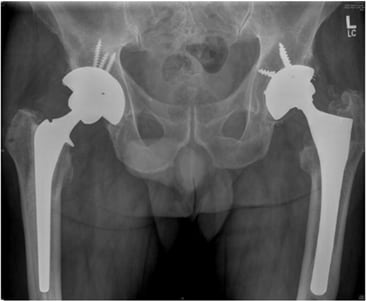

結果、人工股関節置換術を受けました。

でも、骨盤側にはビスのようなもので人工物を留めたり、

大腿骨頭に代わるものを

大腿骨の中にグサッと差し込むわけだけれど、

そもそも骨密度が乏しいわけだから、

ぐらつかないのかなと心配になります。